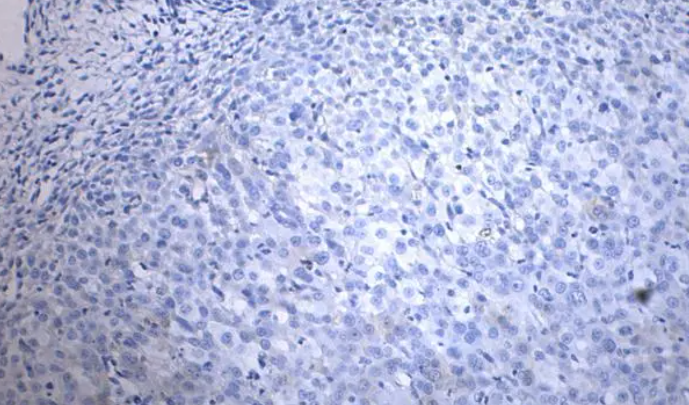

免疫组化检测的原理基于抗体与抗原之间的特异性结合。通过特异性的抗体与肿瘤标记物结合,形成“抗原-抗体”复合物。接着,在辅助试剂的作用下,利用免疫荧光、酶标记或金标记等方法,对抗原-抗体复合物进行检测,从而获得目标标记物的定位信息。

2. 显微观察:利用荧光染色或显色技术,可以通过光学显微镜观察标记物的位置、形态和数量,提供直观的视觉信息。